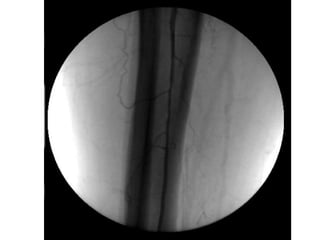

ISQUÉMIA CRÍTICA TRATAMENTO - Revascularização Cirurgia convencional Cirurgia endovascular - Proximal - Distal - Multisegmentar

ISQUÉMIA CRÍTICA TRATAMENTO- Revascularização Cirurgia convencional Cirurgia endovascular - Proximal - Distal - Multisegmentar